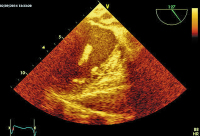

Abbildung 3: Der "fixierte" Teil des Thromboembolus mit dem Durchschnitt vom rechten in den linken Vorhof.